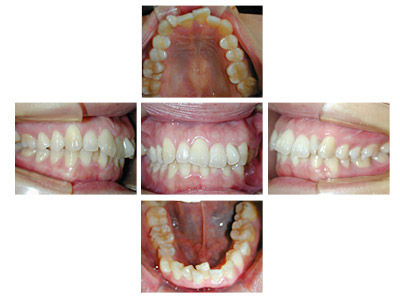

常滑市小林町在住 S.T様(15歳女性)

S.T様は下顎前歯の叢生が主訴でお母様と無料矯正相談で来院されました。

口を閉じる際に口元の緊張があり、横顔に突出感がありました。

以前に上顎前歯の部分矯正をされたご経験があるとお話しされておりました。

そのためか上顎犬歯の横幅(幅径)が通常より少なく思いました。

試料採取より診断の結果、上顎の前歯にも軽度の叢生があり、口元の緊張を改善し、

前歯の叢生の治療のために抜歯が必要であることを説明し、了承が得られたので本格矯正で治療をすすめることとなりました。

上顎前歯に軽度の叢生、下顎前歯に叢生がみられます前歯の上下の接触状態が緊密でなく軽度の舌癖の存在を疑います。

臼歯部は1歯 対 2歯で咬んでいます。

各ステージで順調に治療がすすみました。

治療は順調に進みました。

犬歯の幅径が狭い事の対応として犬歯にダイレクトボンディングを行う、

下顎前歯のストリッピングを行うなどのプランを考えましたがその両方とも行うことなく動的治療を完了しました。

舌癖の存在は後戻りの大きな原因となりますので今後の保定治療でも注意が必要で、引き続き舌癖の改善を行います。

治療期間:2年3ヶ月

治療費用:60万円